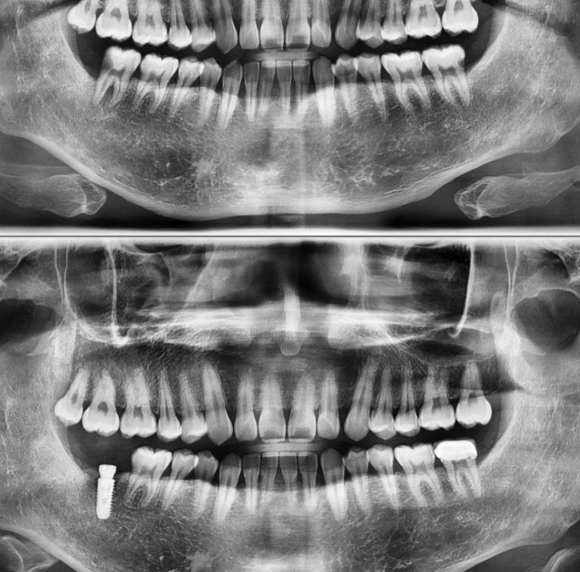

40대 남자 환자로 예전 사랑니로 인한 앞 치아의 방치된 심한 충치로 치아의 뿌리까지 충치가 이환되고 신경치료와 크라운으로 해결되지 않는 통증으로 발치 후 임플란트를 하게된 케이스 입니다. 질환 초기에 치료를 했다면 본인 치아를 살릴 수 있었겠지만 방치를 해둠으로 인해 충치가 커지고 살릴 수 없는 상태가...

40대 남자 환자로 예전 사랑니로 인한 앞 치아의 방치된 심한 충치로

치아의 뿌리까지 충치가 이환되고 신경치료와 크라운으로 해결되지 않는 통증으로

발치 후 임플란트를 하게된 케이스 입니다.

질환 초기에 치료를 했다면 본인 치아를 살릴 수 있었겠지만

방치를 해둠으로 인해 충치가 커지고 살릴 수 없는 상태가 되어버린 안타까운 케이스 입니다.